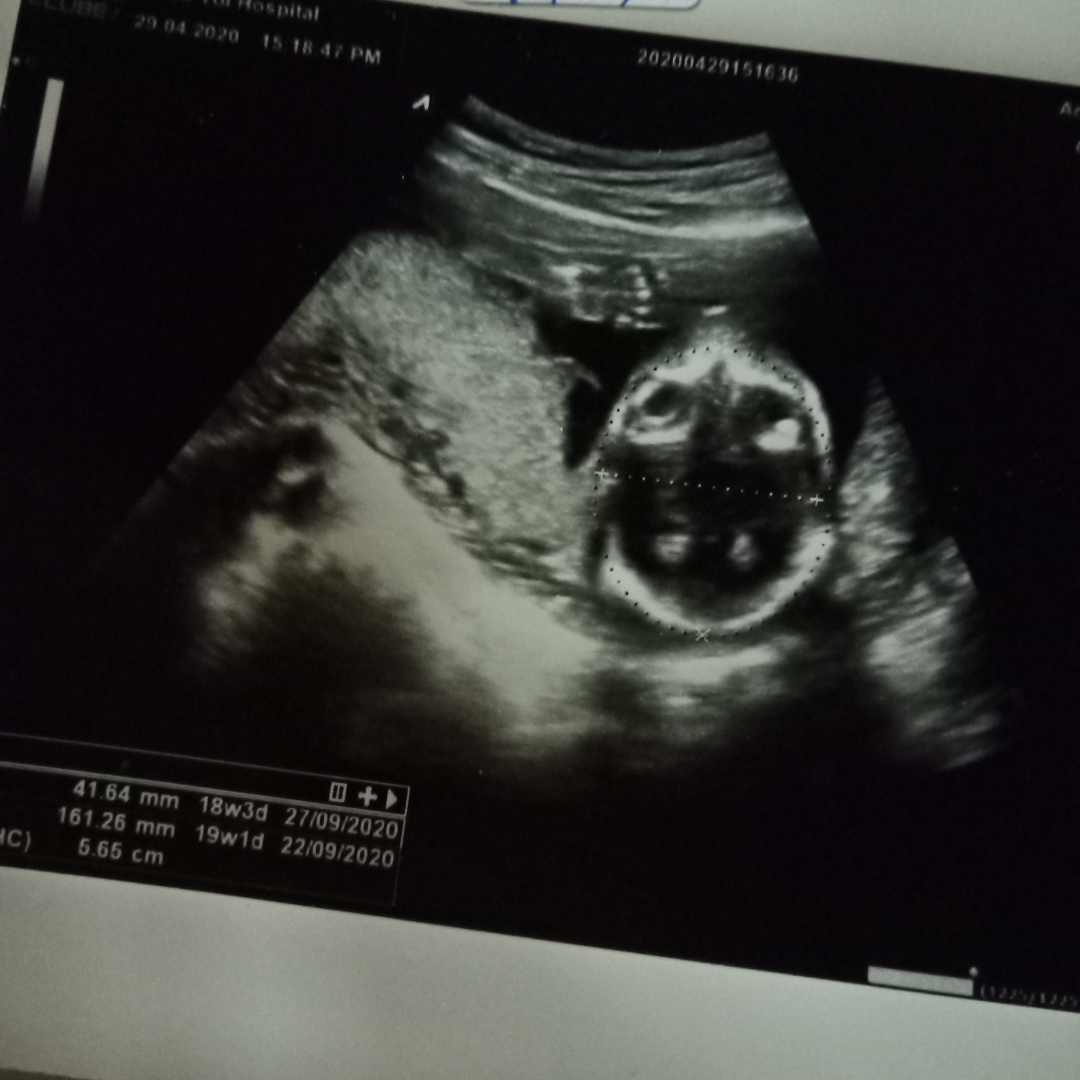

ช่วยดูเพศลูกหน่อยค่ะ

ช่วยดูเพศลูกหน่อยค่ะ ดูยังไงก็ดูไม่ออก